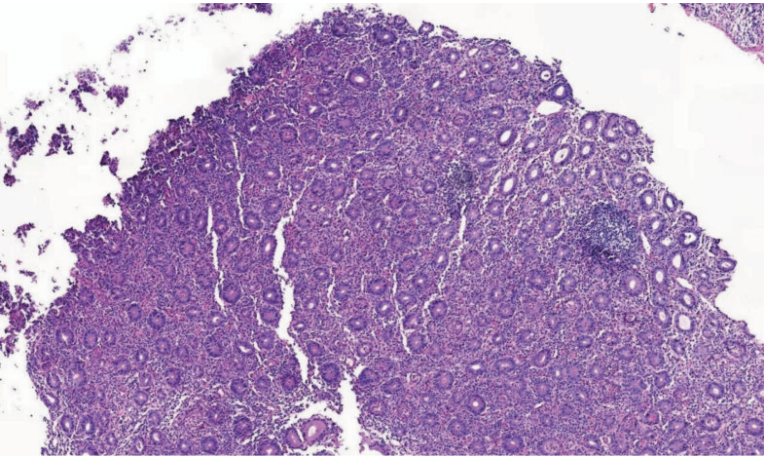

病理 小肠(十二指肠)绒毛重度萎缩,杯状细胞、帕内特细胞明显减少,上皮内少许淋巴细胞浸润,浆细胞无明显减少,符合自身免疫性肠病(图2)。

图2 十二指肠降部黏膜活检病理结果:小肠(十二指肠)绒毛重度萎缩,杯状细胞减少(10×)